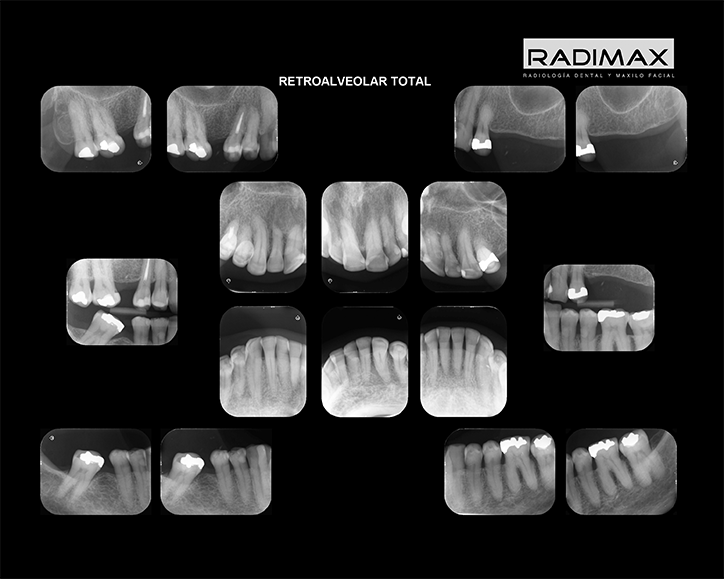

Todas nuestras prestaciones están orientadas a proveer la mejor imagen e informes diagnósticos del territorio Oral y Máxilo Facial, entre las que se cuentas técnicas retroalveolares, radiografías panorámicas, telerradiografías y estudios radiográficos de articulaciones témporo mandibulares (ATM)

Retroalveolar Piezas

Retroalveolar Total

Bite wing Der Izq